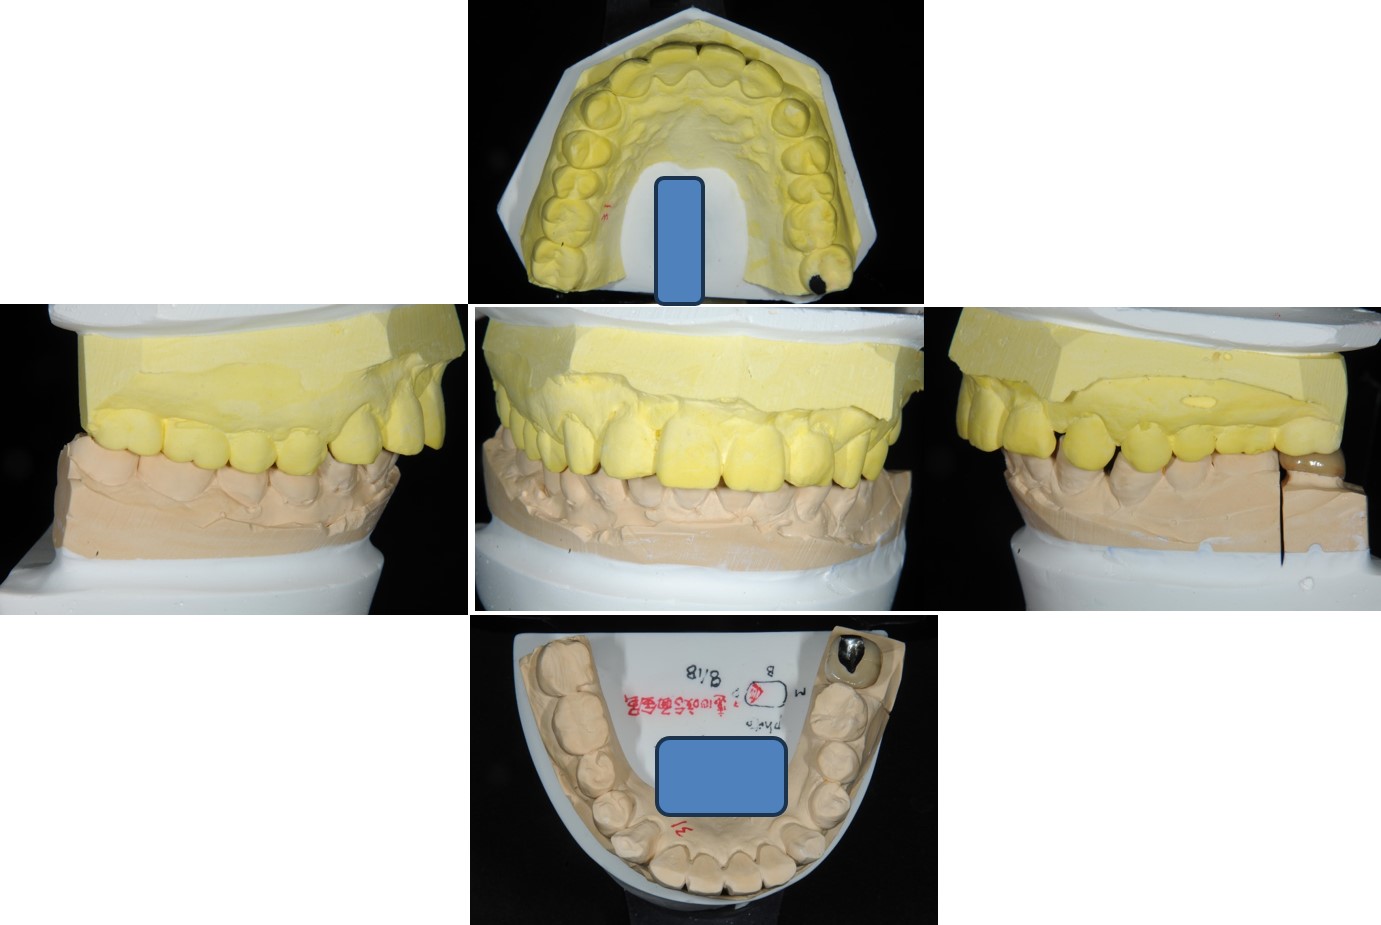

面弓轉移、上咬合器

技師於咬合器上製作金屬燒付瓷牙